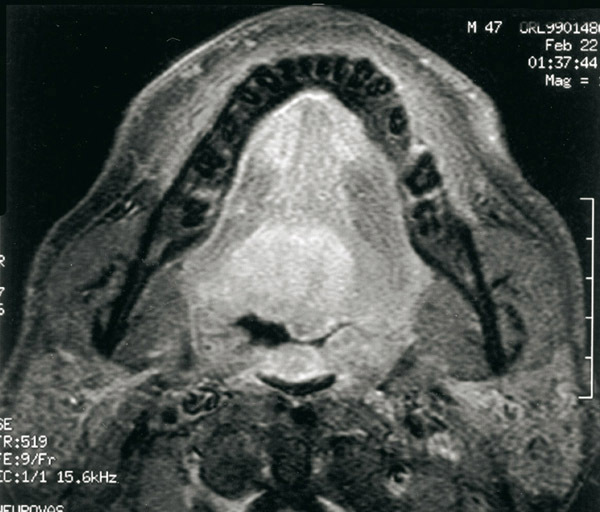

Tumeur de la base de la langue

IRM de base de langue : tumeur infiltrante.